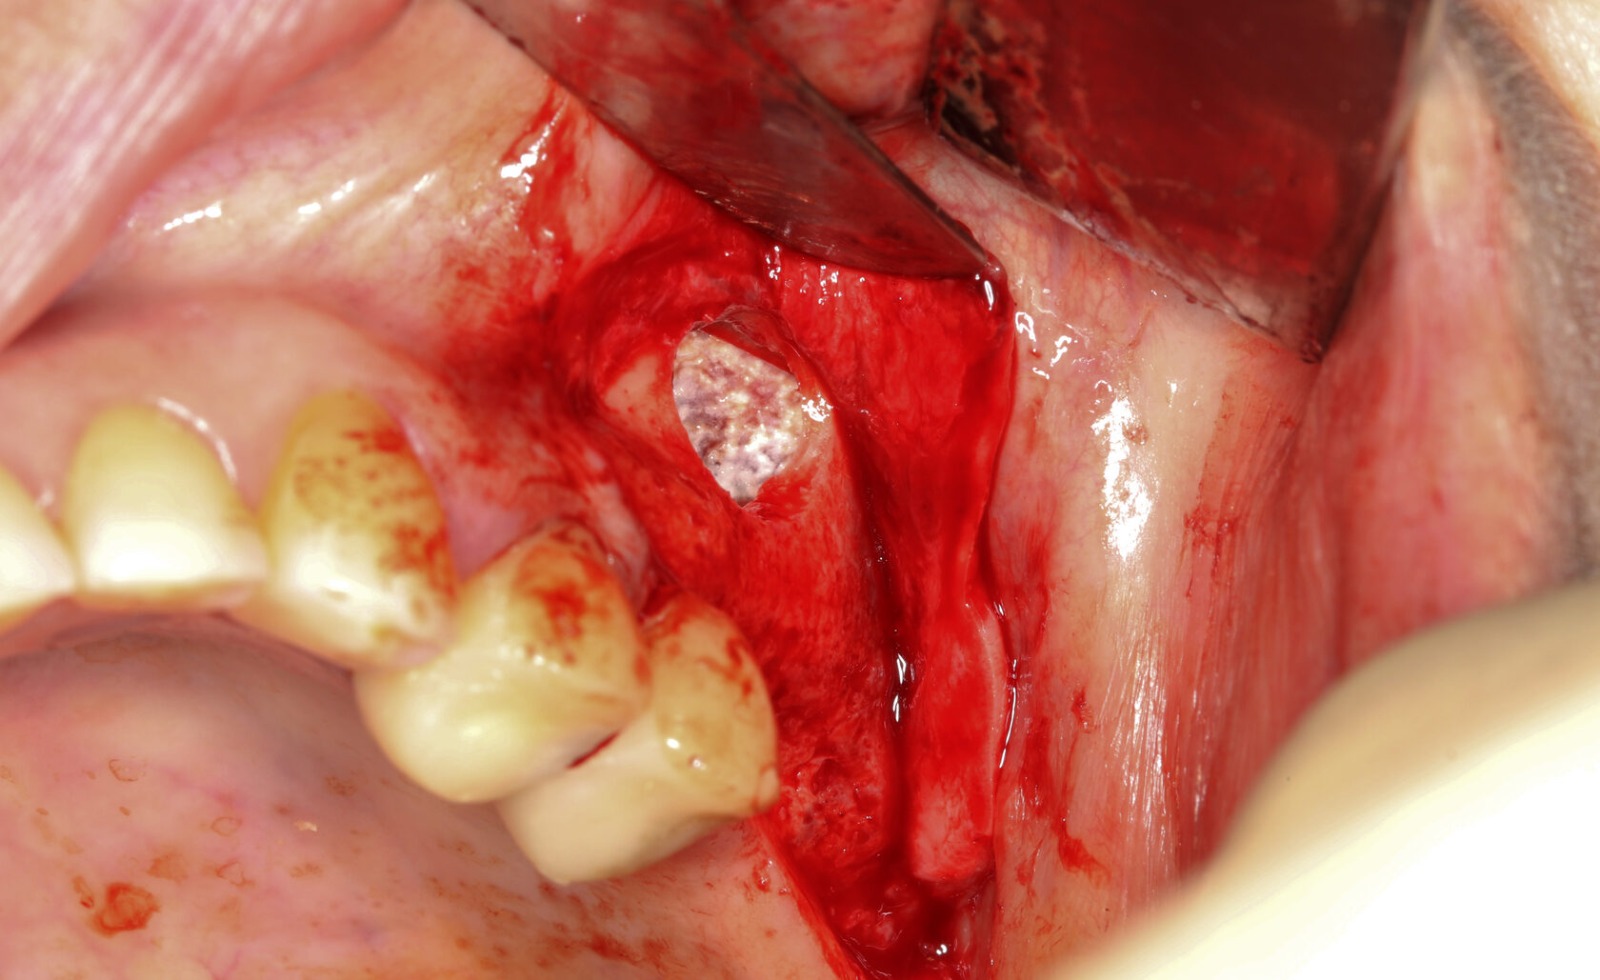

Фотографии учебного материала